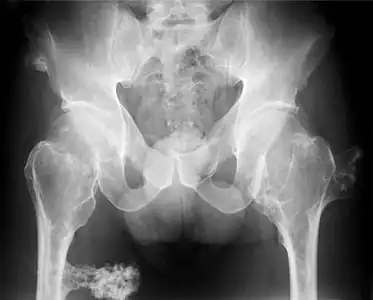

multiple osteochondromas at the pelvis